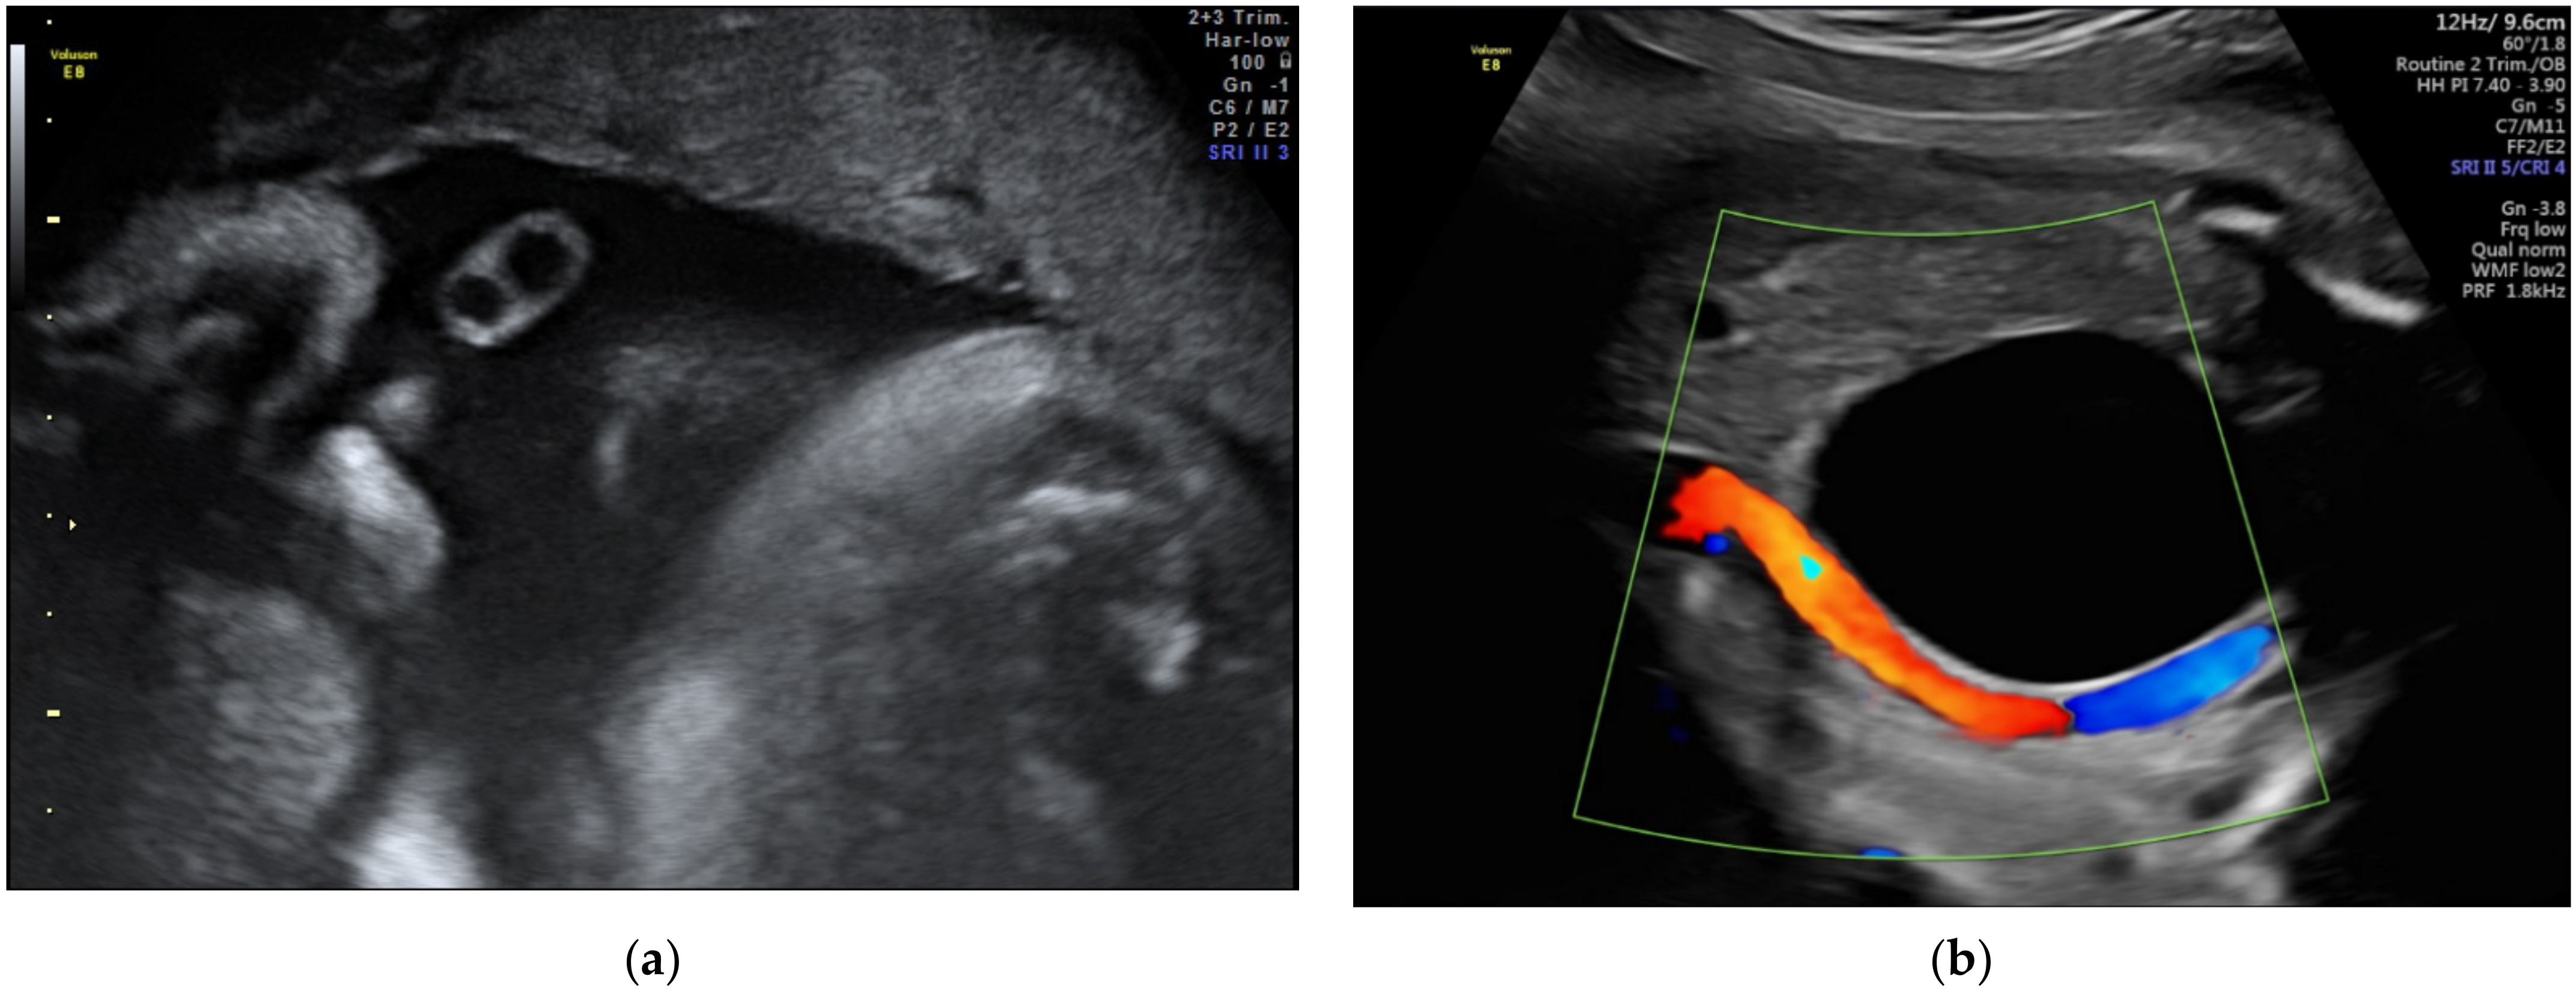

2.4. Anomalies of the Fetal Abdominal Cord Insertion